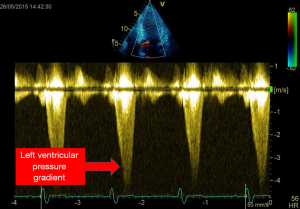

dP/dt on mitral regurgitation

We demonstrated that all volunteers, in whom we performed TTE, a small mitral regurgitation was present (23) V体育官网. Because mitral regurgitation velocity changes during systole is related to the change of intra ventricular pressure, dP/dt could be easily assessed this flow recorded using continuous wave Doppler (Figure 5). By measuring the duration time (dt) between the velocity of 1 m/s and the velocity of 3 m/s (dP of 32 mmHg) on the mitral regurgitation envelop it becomes easy to diagnose any LV systolic dysfunction (normal ranges 800–1,200. This approach was well validated (24,25).